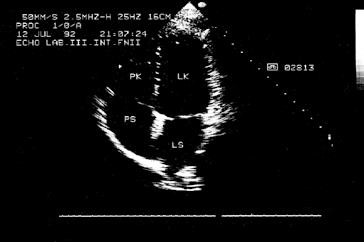

Kromě nakladatelství a výtvarníka se o definitivní podobu třetího dílu učebnice zasloužili mnozí odborníci. Za poskytnutí rtg snímků jsem již od vzniku 1. vydání 3. dílu učebnice vděčný Radiodiagnostické klinice 1. LF UK a paní doc. MUDr. Běle Drugové, DrSc., z radiodiagnostického oddělení Nemocnice Na Homolce. Za vynikající mikrofotografie z vývoje oka děkuji panu prof. MUDr. Františku Vrabcovi, DrSc., který mi je poskytl pro tuto knihu. Panu prof. MUDr. Oldřichu Eliškovi, DrSc., a paní doc. MUDr. Miloslavě Eliškové, CSc., děkuji za poskytnutí podkladů z jejich studií pro vytvoření obrazů mízního odtoku ze srdce. Panu doc. MUDr. Jaromíru Hradcovi, CSc., ze III. interní kliniky 1. LF UK děkuji za poskytnutí echokardiografických obrazů srdce. Upřímně děkuji též oběma spolupracovníkům, panu prof. MUDr. Rastislavu Drugovi, DrSc., a panu prof. MUDr. Miloši Grimovi, DrSc., za porozumění a sympatickou spolupráci na tomto vydání knihy. Studentům, učitelům anatomie i lékařům přeji, aby jim kniha sloužila jako užitečný průvodce a pomocník při studiu tohoto náročného oboru.